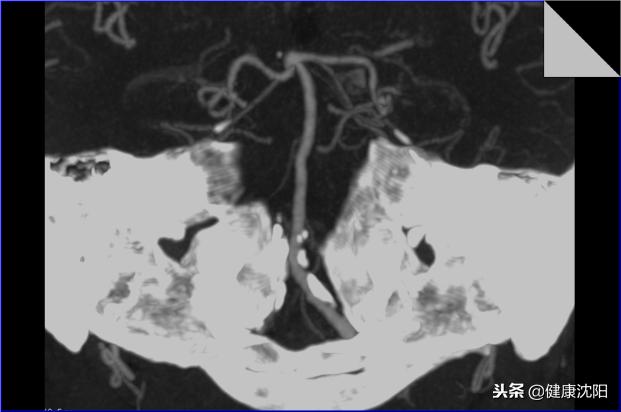

简单地说就是将高于一定阈值密度的影像投影在平面上显像的一种方法,由于这种处理技术对高密度的影像较为敏感,所以它对血管壁上的高密度斑块显示较明显,此外它也可以判断血管是否狭窄或扩张,显示病变,以及血管的平面解剖关系。

显示椎-基底动脉-大脑后动脉系统血管的平面解剖

显示椎-基底动脉-大脑后动脉血管解剖以及血管壁的钙化